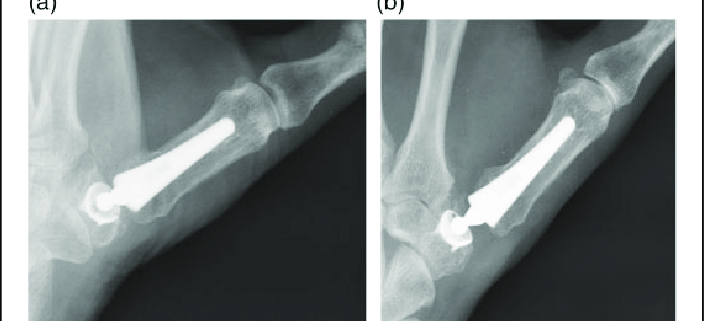

2. Metacarpophalangeal (MCP) Joint Arthroplasty: This procedure involves replacing the joint in the middle of the thumb. It’s commonly performed for individuals with rheumatoid arthritis affecting this joint.

The diagnosis generally involves a physical examination, discussion of symptoms, and medical history review. Imaging tests such as X-rays or Magnetic Resonance Imaging (MRI) can aid in assessing the extent of joint damage and help determine the most suitable treatment option.